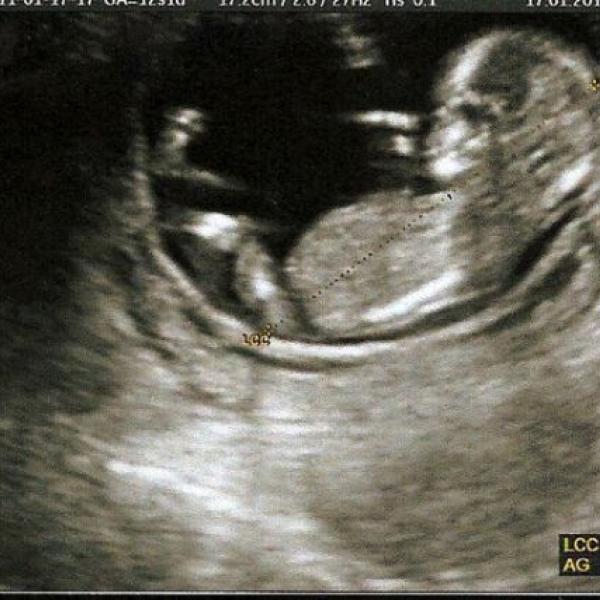

tak vam rychlu pisu, ze jsem v nemocnici od vcerejska kvuli tem mym nekonecnym kontrakcim. Mam kapacku proti zastaveni a 2krat injekce pro vyvinuti plic naseho zlaticka. Verim, ze se mu jeste u maminky libi, jen ho to tvrdnuti delohy asi taky pekne stve, protoze mu to ubira misto na jeho kopaci hry:-)